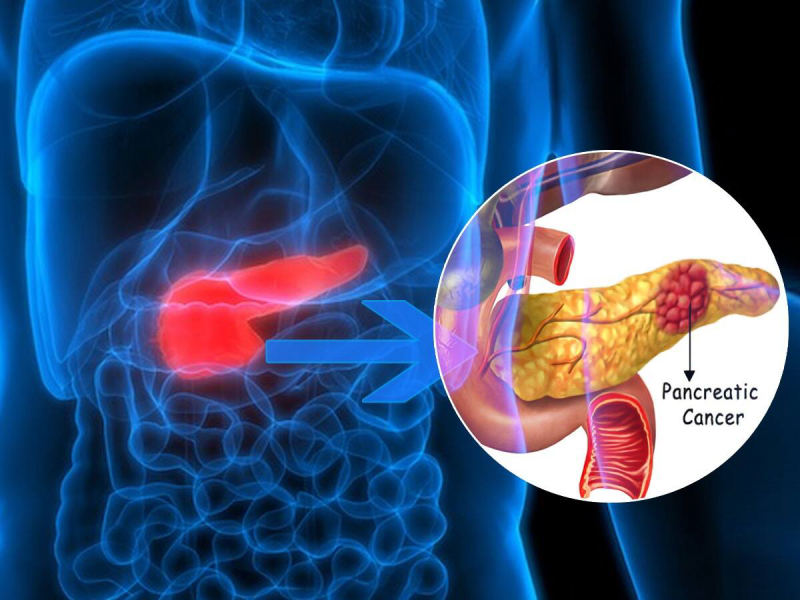

Tumors & Cancers

Discover symptoms & explore medicines and treatment options. Also read expert health articles about symptoms, the latest research, medicines and alternative treatments for every disease and medical condition.